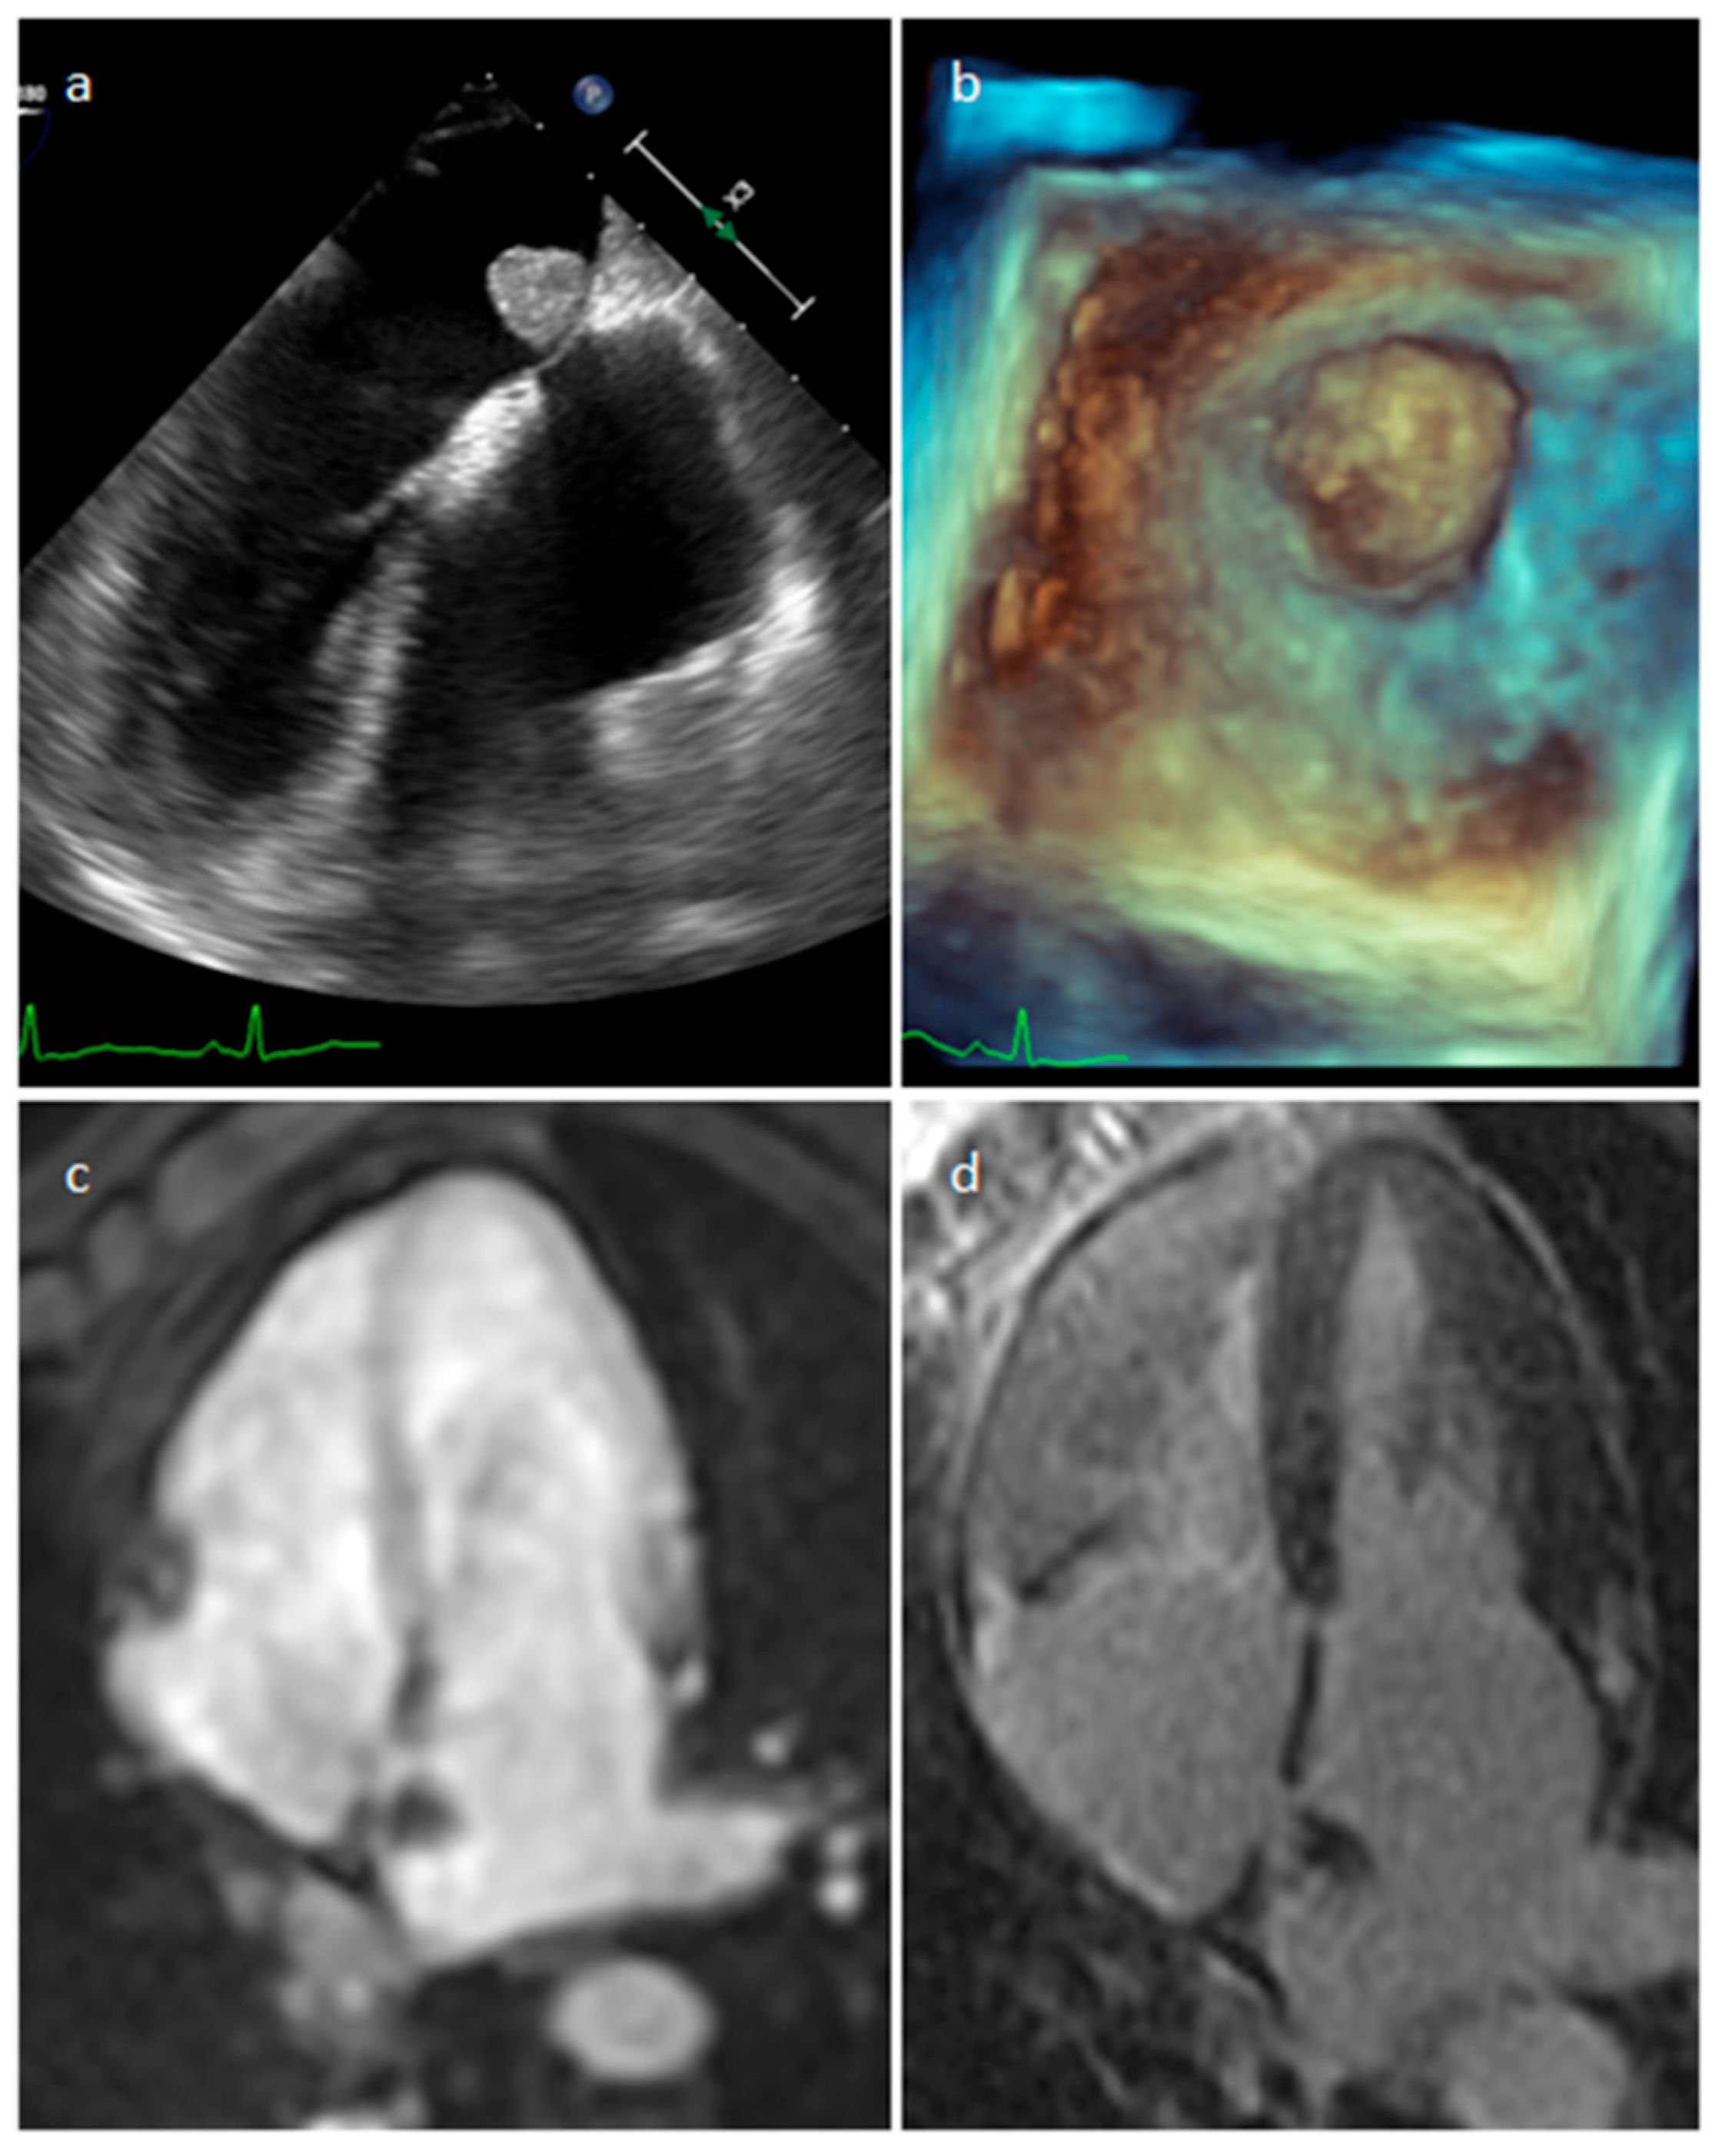

4.1. Myxoma

| Myxoma | Adulthood. Carney complex. | LA | Usually, asymptomatic. Rarely, intracardiac obstruction, embolic events and constitutional symptoms | Mobile mass arising from the IAS | Globular or spherical, with a friable surface and heterogeneous internal echogenicity | Heterogeneous, low attenuation, may be calcified | Isointense T1w, High T2w, heterogeneous LGE |